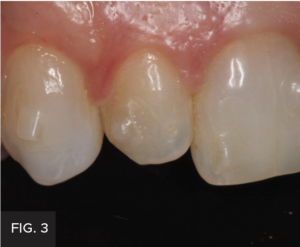

Examination and images, including the prescribed series of AACD photographs,2 revealed that #7 was normal, but smaller in crown size than ideal. Some tissue inflammation, likely related to orthodontic attachments, was visible on the tooth’s distal surface.The photographs and clinical data were reviewed with the patient. The main esthetic challenge would be to recreate incisal translucency and characteristics. (FIG 1 & 2)

Post-operative full smile view after orthodontic treatment completed and shows the completed composite restoration.